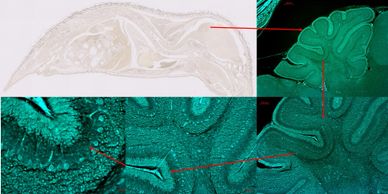

¿Necesitas capturar micrografías y/o de curvas espectrales? Nuestro servicio de captura de imágenes es la solución; nuestros expertos trabajan para lograr esa imagen digna de una portada de revista